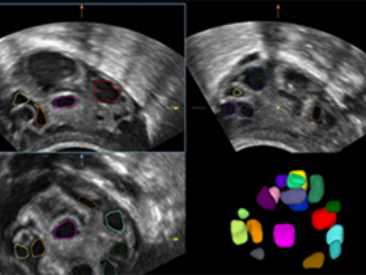

ImĂĄgenes clĂnicas